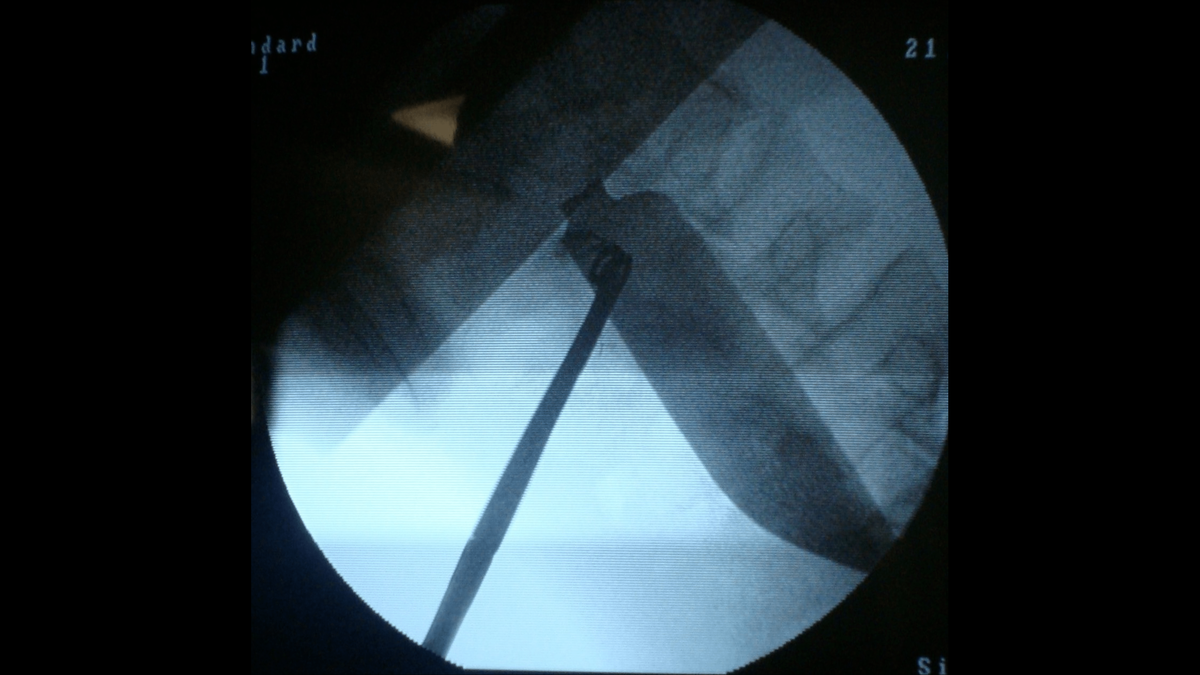

Inside of the man’s abdomen, across the body from the stab wound, was a nearly half-foot-long blade.

“The retained knife blade is an unusual and spectacular injury. Retained stabbing instruments are seldom encountered in patients and have rarely been reported in the literature,” doctors said in the case report, titled The Wandering Blade.

Somehow over the course of 24 hours from when the man was stabbed to when he showed up in the emergency room, the roughly six-inch blade had “wandered” through his abdominal cavity from one side of his body to the other.

“The wondrous part was that the knife blade had traveled to the left iliac fossa without injuring any surrounding (internal organs),” the doctors said.